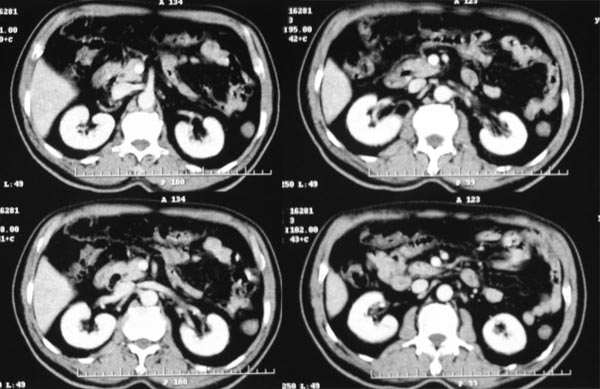

患者,m,71y,乏力、纳差、巩膜黄染两月余,b超示肝内占位性病变。

平扫

1.临床资料:71y,乏力、纳差、巩膜黄染两月余。

2.病灶特点:平扫呈低密度,密度不均,中央呈更低密度;动脉期病灶周围强化较明显,高于正常肝组织,低于同层主动脉密度,中央坏死区未见明显强化;门静脉期,病灶呈低密度,低于正常肝组织密度。

3.诊断:符合肝细胞癌。

临床:患者,m,71y,乏力、纳差、巩膜黄染两月余,b超示肝内占位性病变。

病灶特点:1、平扫:肝右叶大片状低密度影,内见更低密度影,边界不清